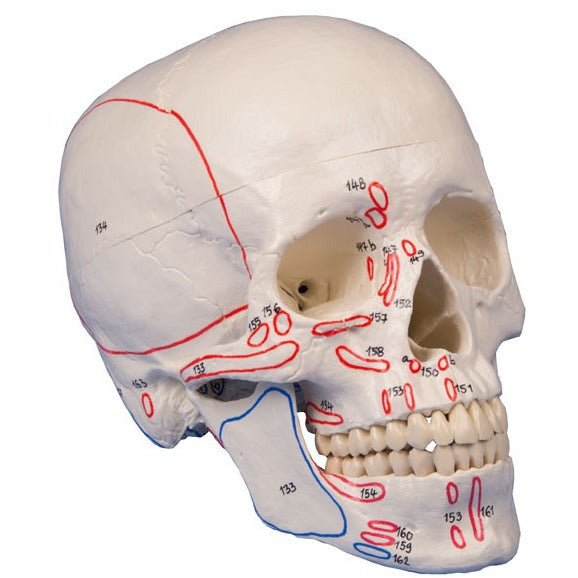

Developing this lifelike reproduction of a human skull we have used the latest technology to digitalize a real human skull and idealized it under the aspects of medical education. This means the skull was adjusted to be anatomically ideal, all anatomical details and structures are present and correspond to anatomical teaching. The three part model consists of skull base, skull cap and lower jaw. The teeth correspond with real dentition concerning position and embrasure. The lower jaw is movably mounted and can be removed. The skull cap is aligned with the skull base using metal pins and held by strong magnets. Due to this there is no need for disturbing hooks, no plastic pins that could break and no risk of having a gap between skull cap and skull base. This distinguishes the model from competitor’s skulls with plastic pins and disturbing metal hooks. The model corresponds with an average European adult concerning size and proportions.

Additionally with marking of muscle insertions and origins. With nomenclature.